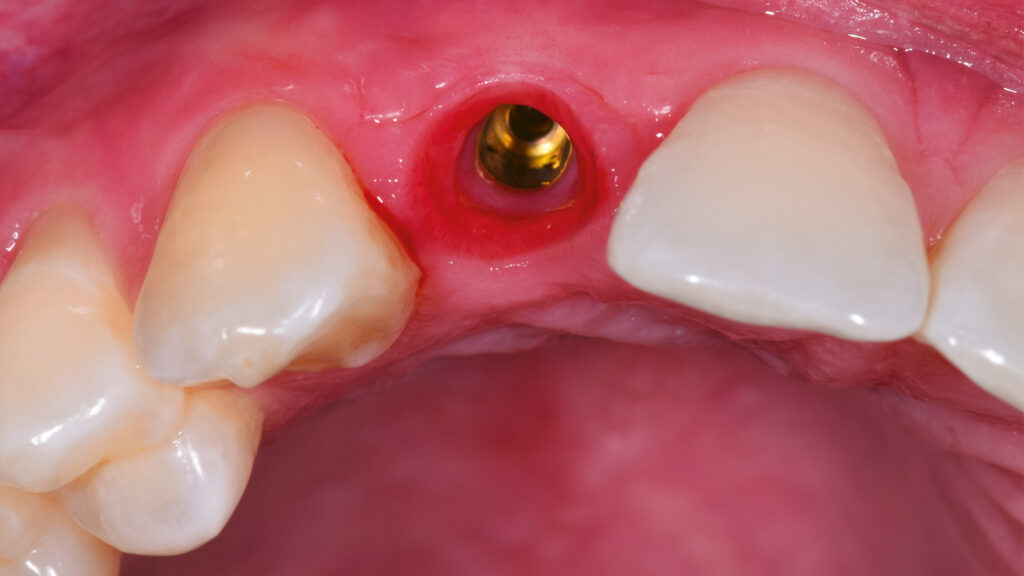

In der Zahnarztpraxis wird der Milchzahn schonend extrahiert und das TempShell-Provisorium mit seinen zwei Flügeln im Mund des Patienten einprobiert (Abb. 38). Nach der Sofortimplantation des Implantates regio 12 erfolgt eine Konturverbesserung, die im Rahmen der Freilegung korrigierend zur Weichgewebsverdickung vorgenommen wird. Dadurch soll ein graues Durchschimmern des Titans verhindert werden (Abb. 39). Einige Wochen später kommt der Patient zur Kontrolle in die Praxis. Die Heilung der Gingiva ist gut. Das Gingivaniveau konnte weiter nach apikal gelegt werden, um einen harmonischeren Gingivaverlauf zu erzielen (Abb. 40 und 41).

Nach der Heilung des Weichgewebes sind die arkadenförmige Kontur der Gingiva und die Papillen deutlich zu erkennen (Abb. 42 und 43). Etwa sechs Monate nach der Osseointegration und Konditionierung der Gingiva wird die Situation mit dem Intraoralscanner erfasst, um mit der Herstellung der implantatprothetischen Versorgung fortzufahren. Nach dem Aufschrauben des Scanbodys auf das Implantat erfolgt der Scanvorgang (Abb. 44). Intraoralscanner gehören zu den aufregendsten neuen Technologien in der Zahnmedizin. Die digitale Abformung bietet dem Patienten deutlich mehr Komfort. Zudem werden klinische Abläufe vereinfacht und die Kommunikation mit dem Zahntechniker verbessert. Im nächsten Schritt werden die STL-Dateien für den Modelldruck aufbereitet (Abb. 45). Vor dem Scannen der gedruckten Modelle muss das Modellanalog regio 12 eingesetzt werden. Das Modell mit abnehmbarer Gingivamaske ist für die Aufnahme des Modellanalogs durch eine Öffnung vorbereitet und besitzt im unteren Bereich des Ausschnittes eine Art Verriegelungsmechanismus (Abb. 46). Dies gewährleistet einen sicheren Presspassung und eine korrekte, automatisch zentrierte Einschubposition (Abb. 47).